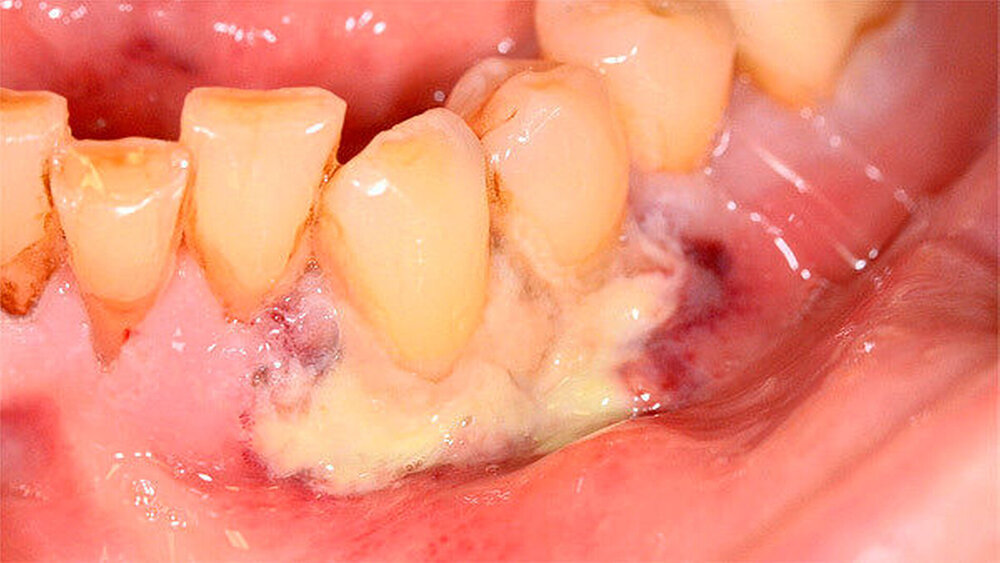

Intraoraler Befund

Der intraorale Befund zeigte neben einer moderat chronischen Parodontitis ein nekrotisierendes und ulzerierendes Schleimhautareal in regio 32 bis 35 (Abbildung 1). Überdies konnte eine Sondierungstiefe von 6 mm zwischen 32 und 33 sowie ein Lockerungsgrad von 1 bis 2 an den Zähnen 32 bis 34 bei positiver Sensibilität erhoben werden, wobei zumindest 2D-radiologisch kein Knochenabbau vorlag (Abbildung 2). Aufgrund des deutlich reduzierten Allgemeinzustandes des Patienten entschieden wir uns für eine stationäre Weiterbehandlung. Ein kurz darauf angefertigtes Blutbild zeigte unter anderem einen Hämoglobin-Wert von 5,2 mmol/l (Referenzbereich 8,6 bis 12 mmol/l), einen Hämatokrit-Wert von 0,24 (Referenzbereich 0,4 bis 0,51), einen Kernschatten-Wert von 40 Prozent (Referenzbereich 1 Prozent ) sowie einen CRP-Wert von 53,1 mg/l (Referenzbereich 5 mg/l).